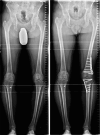

Results: The follow-up period was 24 (6-81) months. The follow-up rate was 73% (27/37). The preoperative leg axis in group one showed an average valgus of 15.9° (9-40°). Group two had an average varus of 12° (8-21°). Postoperatively, the leg axis was 3.4° varus in group one and 0.5° valgus in group two. The mLDFA changed in group one from 83.2° to 90.9°, the MPTA from 95.5° to 87.0°. In group two, the mLDFA changed from 91.9° to 85.9° and the MPTA from 83.3° to 88.3° on average. The JLCA changed in group one from - 3.2 (- 5°-0°) to - 0.5° (- 3-2°) postoperative and in group two from 3.3° (1-8°) to 3.0° (0-6°) postoperative. Tegner score, Lysholm score and Japanese knee Society score all improved significantly in both groups. Patients with a valgus axis have worse clinical scores before surgery than the varus group, but the varus group shows a higher potential for improvement postoperatively. Every patient stated that they would have the operation performed again. Complications were rare, two overcorrections required corrective surgery. Two hinge fractures were treated intraoperatively with additional contralateral plate osteosynthesis.

Conclusions: Patients show very good clinical results after DLO. The improvements in the valgus knees are greater, but starting from a lower preoperative level, probably due to improvements in both the lateral compartment and the patellofemoral compartment. An important finding was that JLCA is normalizing in valgization DLO but not in varization DLO. This needs to be considered in planning a DLO.